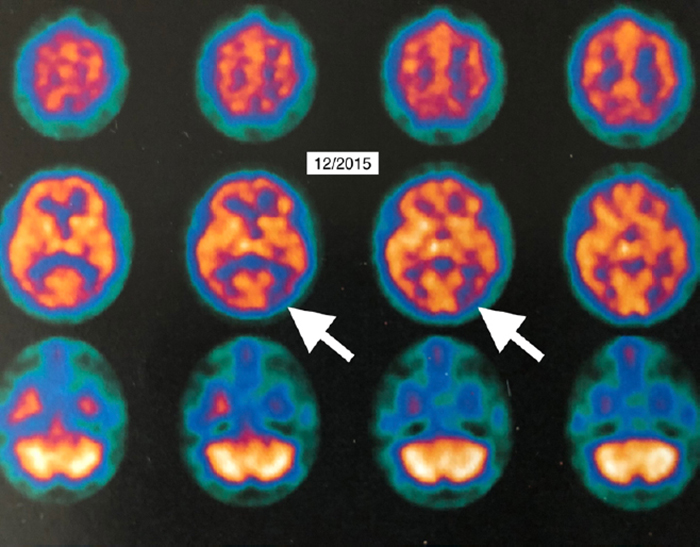

The authors report the case of a 58-year-old female who had experienced five years of cognitive decline, which began accelerating rapidly. Single photon emission computed tomography (SPECT) suggested Alzheimer’s disease. The diagnosis was confirmed by 18Fluorodeoxyglucose (18FDG) positron emission tomography (PET) brain imaging, which revealed global and typical metabolic deficits in Alzheimer’s.

“PET imaging is used around the world as a biomarker in oncology and cardiology to assay responses to therapy,” says Dr. Fogarty. “We now have an irrefutable biomarker system that this intervention has promise where no other real hope for recovery of dementia has ever existed before.”The physicians report that two months post-HBOT, the patient felt a recurrence in her symptoms. She was retreated over the next 20 months with 56 HBOTs (total 96) at the same dose, supplemental oxygen, and medications with stability of her symptoms and Folstein Mini-Mental Status exam.